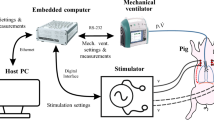

Based on the above requirements, a working prototype of a device for non-invasive stimulation of the phrenic nerve (hereinafter referred to as the device) was developed and constructed. The structural diagram of the device is shown in Fig. 1.

Two independent AC/DC converters are used to provide all the supply voltages required for device operation. One power supply converts the 220 V input voltage into the ± 15 and + 5 V voltages required to operate the control elements and to generate pulses—the microcontroller (MCU), digital-to-analog converter (DAC), multiplexer, operational amplifiers, etc.). The second power supply outputs a voltage of up to 300 V as needed to generate the specified current through loads of 0–15 kΩ.

The device is controlled by an ARM family microcontroller type STM32F303CBT6. The MCU is clocked from a ZQ1 quartz resonator at 8 MHz; its own clock frequency is increased to 72 MHz using a phase-locked loop system. The MCU is programmed via a standard SWD interface using a specialized external programme. For ease of use, the microcontroller firmware can be updated via the USB interface. The MCU is also used to organize communication with a personal computer (PC) via the USB interface using a proprietary protocol. The USB interface circuits in this IC are protected from electrostatic discharges using a circuit design based on USBLC6-2SC6 protective diodes. The circuit also employs blocking capacitors to maintain the instantaneous voltage value in the power circuits at a constant level by blocking noise caused by the fact that the current consumption of the MCU is not constant over time.

A multiplexer allows selection of the direction (channel) for the current generated by the source controlled by the DAC. Thus, use of a multiplexer allows the device to be multichannel, with connections to several patients at the same time.

An electromagnetic relay provides mechanical switching of the output signal to each channel. This switching method increases device safety by ensuring that there are none of the leakage currents inherent in solid-state semiconductor relays.